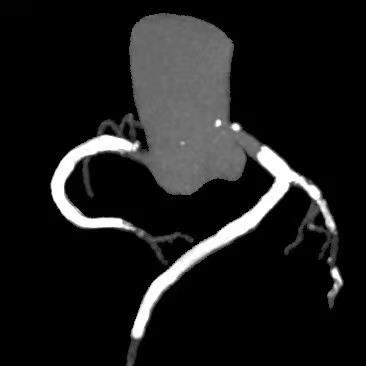

IABP植入后,旋磨导丝顺利经左主干通过病变置于LAD远段,先后使用1.5mm、1.75mm磨头旋磨,而后,在分支均保护的情况下,植入3.0*24mm支架,并选择3.5*12mm NC 30atm行后扩。![]() 先后1.5mm、1.75mm磨头旋磨 ![]() 分支均保护的情况下,3.0*24mm支架植入 然而,虽经NC球囊反复后扩张,左主干支架依然膨胀不良,考虑为钙化厚度过大所致。此时,再行球囊扩张无效、再行旋磨磨头直径不够;为求进一步管腔获得,果断启动Shockwave IVL。为保证IVL球囊与支架及深层钙化紧密贴靠,选取3.5*12mm Shockwave IVL球囊,通过病变后,迅速充盈电解液并扩张至4atm,触发血管内冲击波,每周期10个脉冲、耗时10秒,共行6个周期IVL治疗,之后将脉冲球囊扩张至6atm。复查造影及IVUS,主干最小管腔面积从4.9mm2上升为7.3mm2。随即又在前降支的中远段重度狭窄处顺利植入了2.5*18mm的支架。患者于三天后顺利出院,胸闷症状明显改善,活动耐量显著增加。 ![]() ![]() ![]() 3.5*12mm Shockwave IVL左主干支架内处理前后对比 术者总结